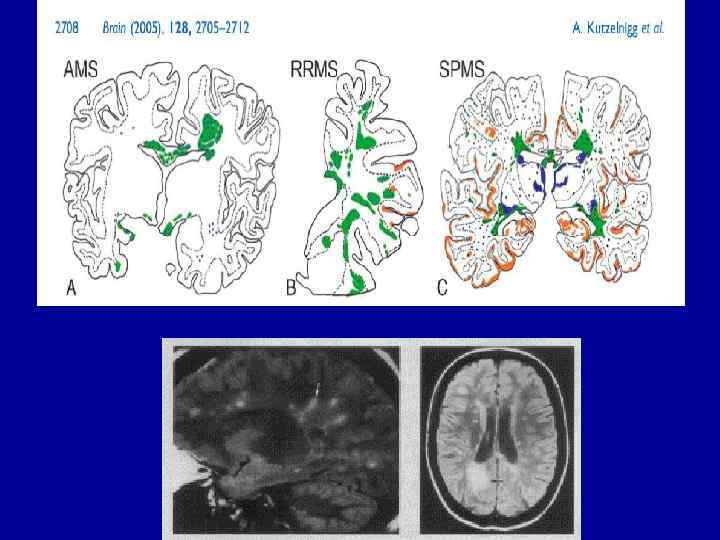

а б Очаги демиелинизации в полушариях (а) и стволе (б) головного мозга с повышением интенсивности сигнала